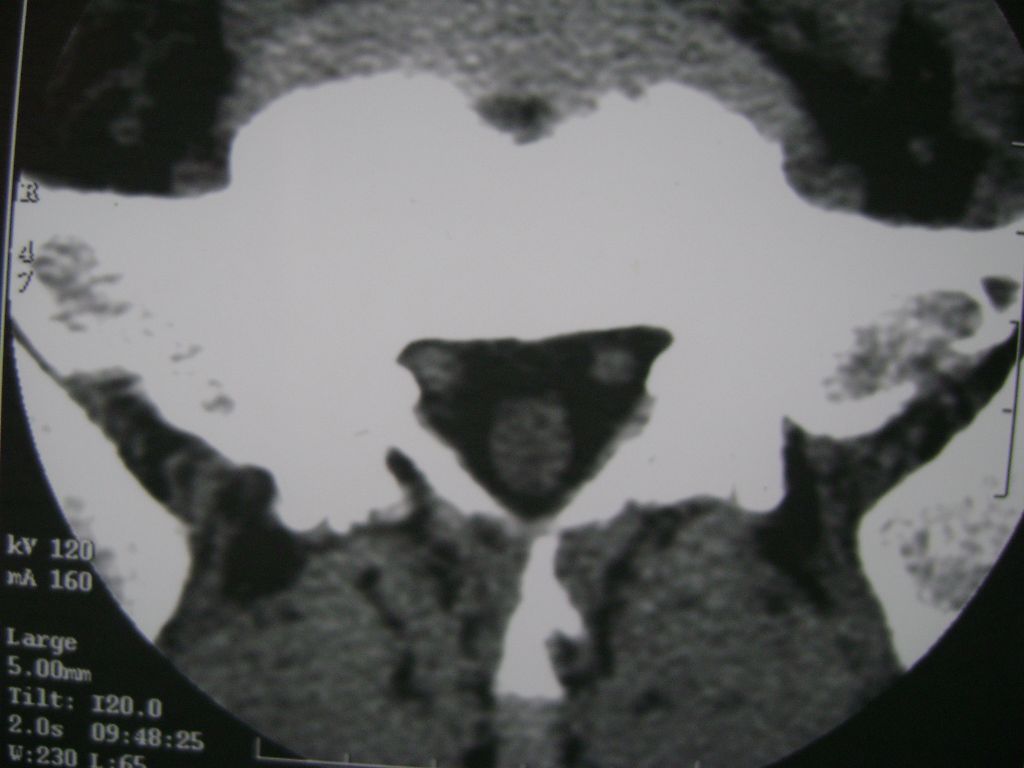

m  50  腰痛

两个椎盘均有膨出及突出改变,下一个尚有椎盘积气,后纵韧带钙化,另椎管脂肪过多症

椎间盘膨出,后纵韧带钙化,骨质增生

两个椎间盘中央型重度突出,黄韧带增厚。

两个椎间盘膨出并突出,下一个椎间盘变性;双侧黄韧带钙化。